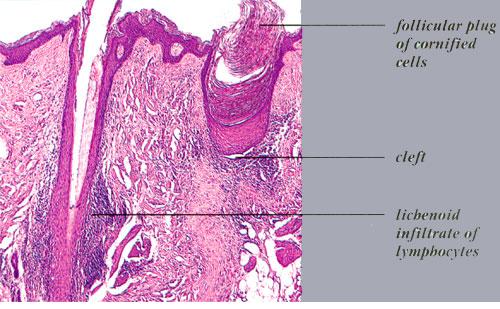

Read MoreAlopecia of Lichen Planus =الحاصة بسبب الحزاز المنبسط